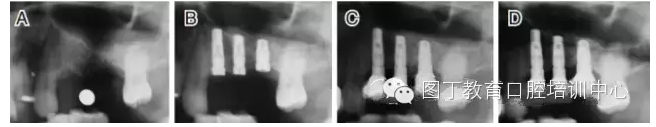

病例3 有骨間隔(圖5)

圖5